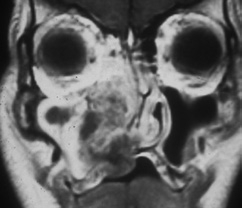

Von dieser Form der Pizerkrankung ist die allergische Pilzsinusitis (AFS, allergic fungal sinusitis) abzugrenzen [16]. Diese immunologische Erkrankung geht mit einer generalisierten NNH-Entzündung (Pansinusitis), Asthma und Polyposis einher (Abb. 12).

Prof. Dr. O. Kaschke